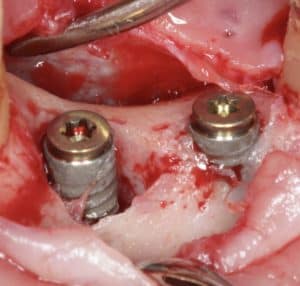

7. Titanium Brushes

A later evolutionary step in implant surface decontamination, the titanium brushes were aimed at eliminating both hard and soft deposits from implant rough surface. As these brushes also remove a superficial layer of titanium from the implant surface, one could see them also as a precursor to implantoplasty. I have used two types of such brushes, one the “vertical” brush and the other being a bristle.

The vertical brush is good in approaching the implant surface parallel with the axis of the implant, or possibly with a narrow angle. That makes it more efficient when the suprastructure can be removed. It is also a good choice to reach the bottom of intrabony defects, which would be unreachable with other instruments. At the same time it’s use in a horizontal angle is limited and thus it’s difficult to apply when there is a bulky prosthesis. It has been for a while a standard tool for intrabony peri-implant defects. My main concern is however that they get blunt very quickly and then become useless. It is a “single use” instrument, but in my hands, it usually takes 1 implant to blunt one brush, so it is a “single implant” rather than a “single patient” tool. Sometimes I cut off the blunt part so that I can use the rest for one more implant, but even so it remains an expensive option.